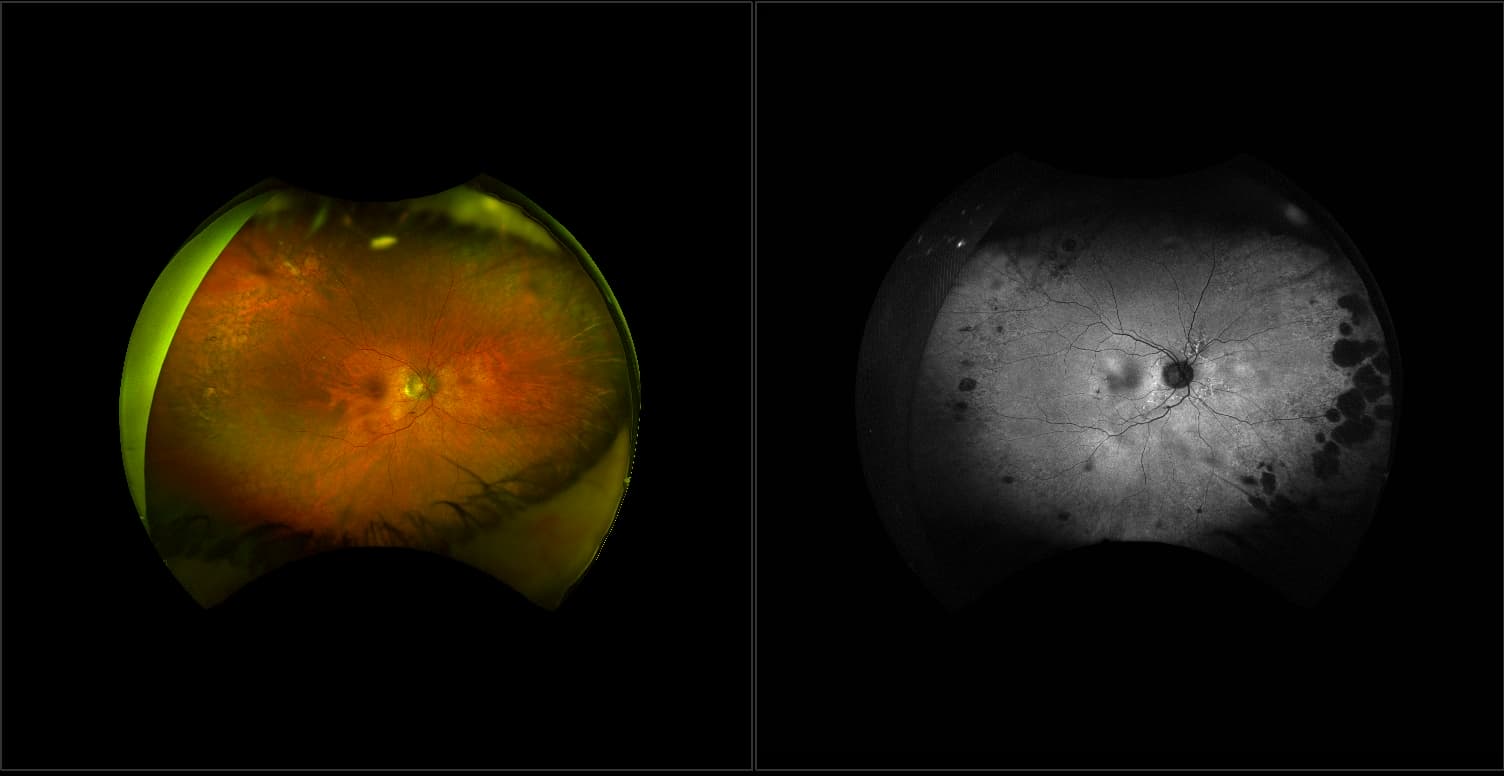

Acute multifocal placoid pigment epitheliopathy (AMPPE)

AMPPE affects otherwise young healthy adults and presents as a disorder affecting the retina, Retinal Pigment Epithelium and choroid. APMPPE is an acquired, self-limiting, inflammatory disorder.